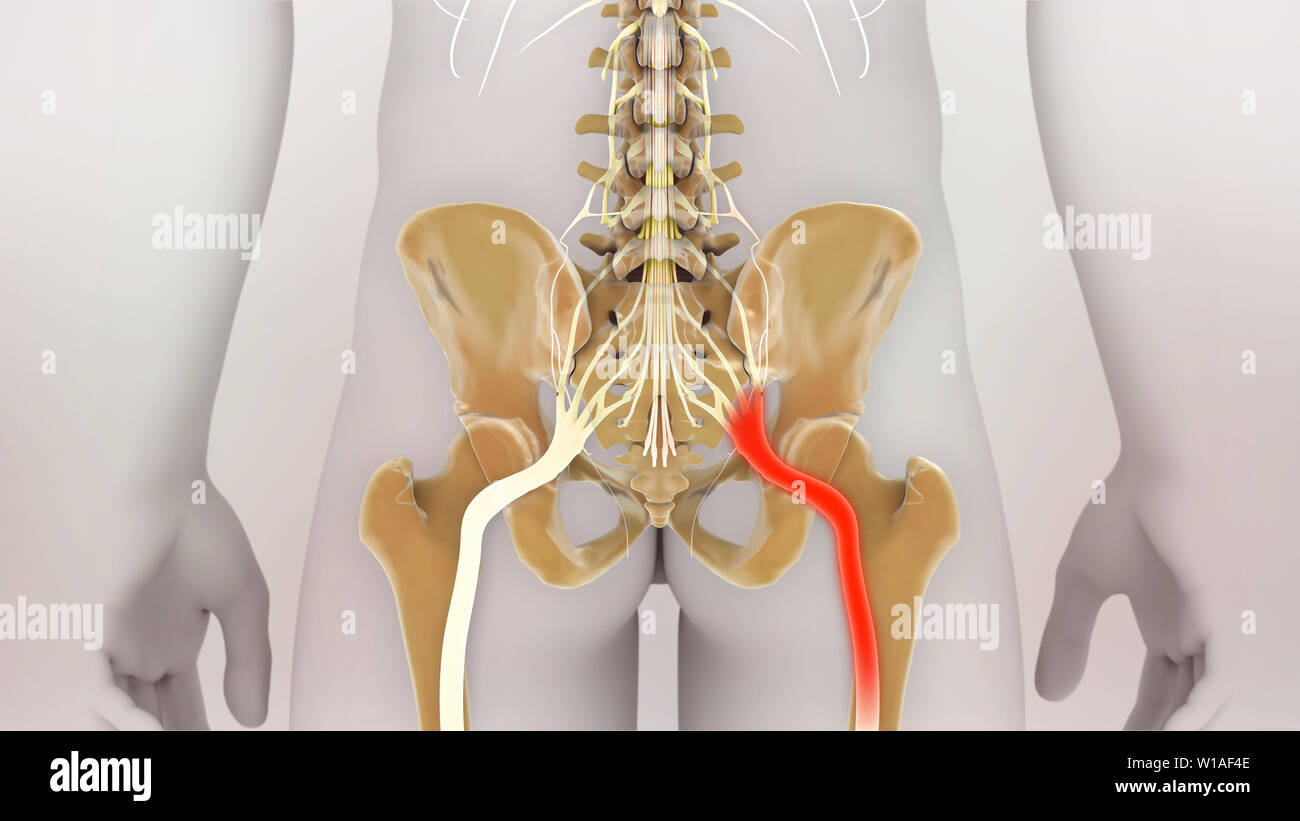

La douleur du nerf sciatique Banque D'Imageshttps://www.alamyimages.fr/image-license-details/?v=1https://www.alamyimages.fr/la-douleur-du-nerf-sciatique-image259001582.html

La douleur du nerf sciatique Banque D'Imageshttps://www.alamyimages.fr/image-license-details/?v=1https://www.alamyimages.fr/la-douleur-du-nerf-sciatique-image259001582.htmlRFW1AF4E–La douleur du nerf sciatique